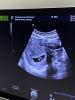

Результаты УЗИ моей звёздочки 💍

ПЯ 12.3мм

Ктр 7.2мм💫

ЖМ 5.3мм

Сб + (включала слушать)🩷

Эндометрий 20мм

Срок по месячным 7 недель, по УЗИ 6н2дня , меня это немного насторожило!